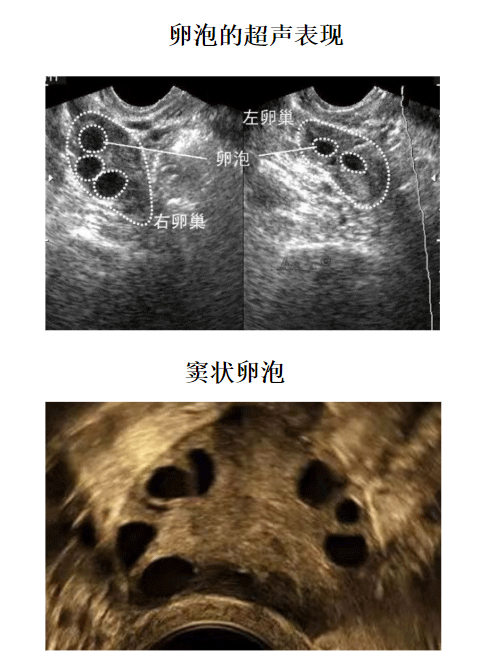

2、多囊卵巢综合征引起的女性不孕,多囊卵巢综合征是引起女性排卵障碍的常见疾病,通过卵泡监测能够发现有很多细小的卵泡,但是不能发育成熟达到排卵要求。

A:如果卵泡监测到卵泡大小在12mm以下的时候,三天一次,当监测到卵泡大小为12mm以上的时候,建议一天监测一次,当卵泡趋近成熟的时候,可能需要一天监测两次,如果一直没有监测到卵泡,也是三天一次,后面根据卵泡数量进行跟进,一直监测到卵泡成熟为止。